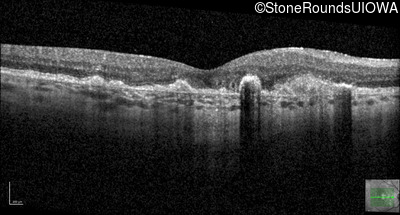

Malattia Leventinese (IIJ)

Malattia Leventinese (IIJ)

This 43 year old woman has experienced a gradual reduction in her central vision for the past 3 years.

| Malattia Leventinese | EFEMP1 | Arg345Trp CGG>TGG | AD |